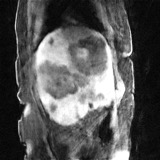

Deep neural networks for medical image reconstruction are traditionally trained using high-quality ground-truth images as training targets. Recent work onNoise2Noise (N2N) has shown the potential of using multiple noisy measurements of the same object as an alternative to having a ground truth. However, existing N2N-based methods cannot exploit information from various motion states, limiting their ability to learn on moving objects. This paper addresses this issue by proposing a novel motion-compensated deep image reconstruction (MoDIR) method that can use information from several unregistered and noisy measurements for training. MoDIR deals with object motion by including a deep registration module jointly trained with the deep reconstruction network without any ground-truth supervision. We validate MoDIR on both simulated and experimentally collected magnetic resonance imaging (MRI) data and show that it significantly improves imaging quality.